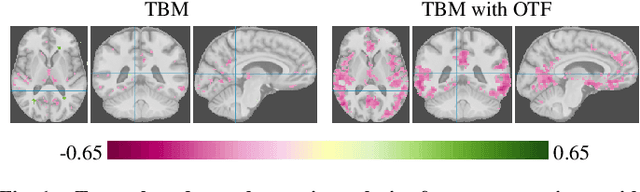

Abstract:Brain pathologies often manifest as partial or complete loss of tissue. The goal of many neuroimaging studies is to capture the location and amount of tissue changes with respect to a clinical variable of interest, such as disease progression. Morphometric analysis approaches capture local differences in the distribution of tissue or other quantities of interest in relation to a clinical variable. We propose to augment morphometric analysis with an additional feature extraction step based on unbalanced optimal transport. The optimal transport feature extraction step increases statistical power for pathologies that cause spatially dispersed tissue loss, minimizes sensitivity to shifts due to spatial misalignment or differences in brain topology, and separates changes due to volume differences from changes due to tissue location. We demonstrate the proposed optimal transport feature extraction step in the context of a volumetric morphometric analysis of the OASIS-1 study for Alzheimer's disease. The results demonstrate that the proposed approach can identify tissue changes and differences that are not otherwise measurable.